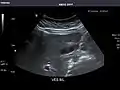

Spleen

Spleen: Normal in size.